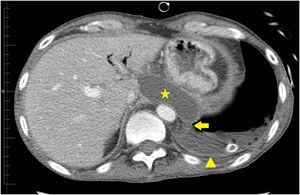

Fue llevado a urgencias de un centro hospitalario por el servicio de emergencias extra-hospitalario en situación de insuficiencia respiratoria hipoxémica grave y obnubilación concomitante. En la radiografía de tórax se apreció un patrón alvéolo intersticial en todo el campo pulmonar derecho y pulmón blanco izquierdo, con desviación de la tráquea hacia la derecha, sugestivo de derrame pleural masivo. Se realizó intubación orotraqueal, tras la cual se colocó un drenaje pleural izquierdo. El paciente persistió con insuficiencia respiratoria grave, apreciándose un patrón alvéolo intersticial bilateral con una imagen de neumotórax izquierdo. Este último, probablemente en relación con la poca distensibilidad pulmonar y la ventilación mecánica. Tras ello se procedió a colocación de otro drenaje pleural izquierdo sin obtener mejoría. Se derivó al paciente a nuestro centro. La bioquímica del líquido pleural fue: glucosa 181mg/dl, proteína de 3g/dl, LDH 528UI/l y amilasa 14.106UI/l. Los resultados microbiológicos de los cultivos (líquido pleural, aspirado traqueal, sangre, orina) fueron negativos. Tras estos resultados, se planteó la posibilidad de FPT. No se observó signos de insuficiencia cardiaca, y la ecocardiografía no apreció alteraciones; así mismo, no presentó afectación de otros órganos, ni respuesta inflamatoria sistémica. Se colocó un tercer drenaje pleural con cierta reducción del neumotórax. Tras ello, el paciente presentó mejoría progresiva, con desaparición del infiltrado alvéolo-intersticial y fue destetado de la ventilación mecánica tras 9 días de estancia en medicina intensiva. Tras ello, se realizó una tomografía computarizada de tórax y abdomen en la que se demostró la FPT (figs. 1 y 2). Posteriormente, el paciente pudo ser dado de alta a domicilio.

La FPT es causada por una disrupción del conducto pancreático, que conduce a la salida de secreciones pancreáticas al tórax, a través del hiato aórtico o esofágico1, provocando un seudoquiste mediastínico2,3, una fístula pancreático-bronquial, una fístula pancreático-pericardial4 o una fístula pancreático-pleural5. La mayoría de los casos de FPT son causados por pancreatitis crónicas. El caso descrito se trata de una fístula pancreático-pleural. Para el diagnóstico se utiliza la tomografía computarizada6, la resonancia magnética, la colangiopancreatografía por resonancia magnética y la colangiopancreatografía endoscópica retrógrada. Siendo estas 2 últimas más precisas para localizar el lugar de disrupción. El abordaje terapéutico, además de la suspensión de la dieta enteral y la administración de somatostatina o octreotide, incluye la colocación de un stent pancreático por vía endoscópica o mediante sutura de la disrupción en cirugía abierta y, por último, el tratamiento conservador7. Este último fue el tratamiento que se utilizó en nuestro caso, con resultado clínico favorable, y que consistió fundamentalmente en drenar el líquido pleural. Decidimos el tratamiento conservador por la buena respuesta inicial que presentó en nuestro centro, tras la colocación del último drenaje pleural. Esa también fue la razón por la que no solicitamos una colangiopancreatografía por resonancia magnética durante su estancia en el servicio de medicina intensiva.